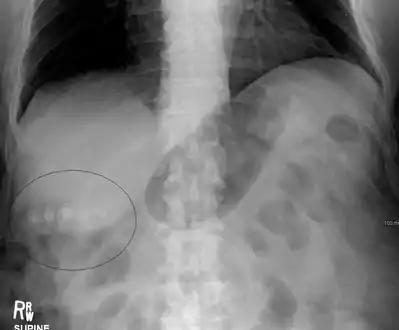

Gallstones as seen on plain X-ray

Mixed (brown pigment stones) typically contain 20–80% cholesterol (or 30–70%, according to the Japanese classification system).[35] Other common constituents are calcium carbonate, palmitate phosphate, bilirubin and other bile pigments (calcium bilirubinate, calcium palmitate and calcium stearate). Because of their calcium content, they are often radiographically visible. They typically arise secondary to infection of the biliary tract which results in the release of β-glucuronidase (by injured hepatocytes and bacteria) which hydrolyzes bilirubin glucuronides and increases the amount of unconjugated bilirubin in bile. Between 4% and 20% of stones are mixed.[3]